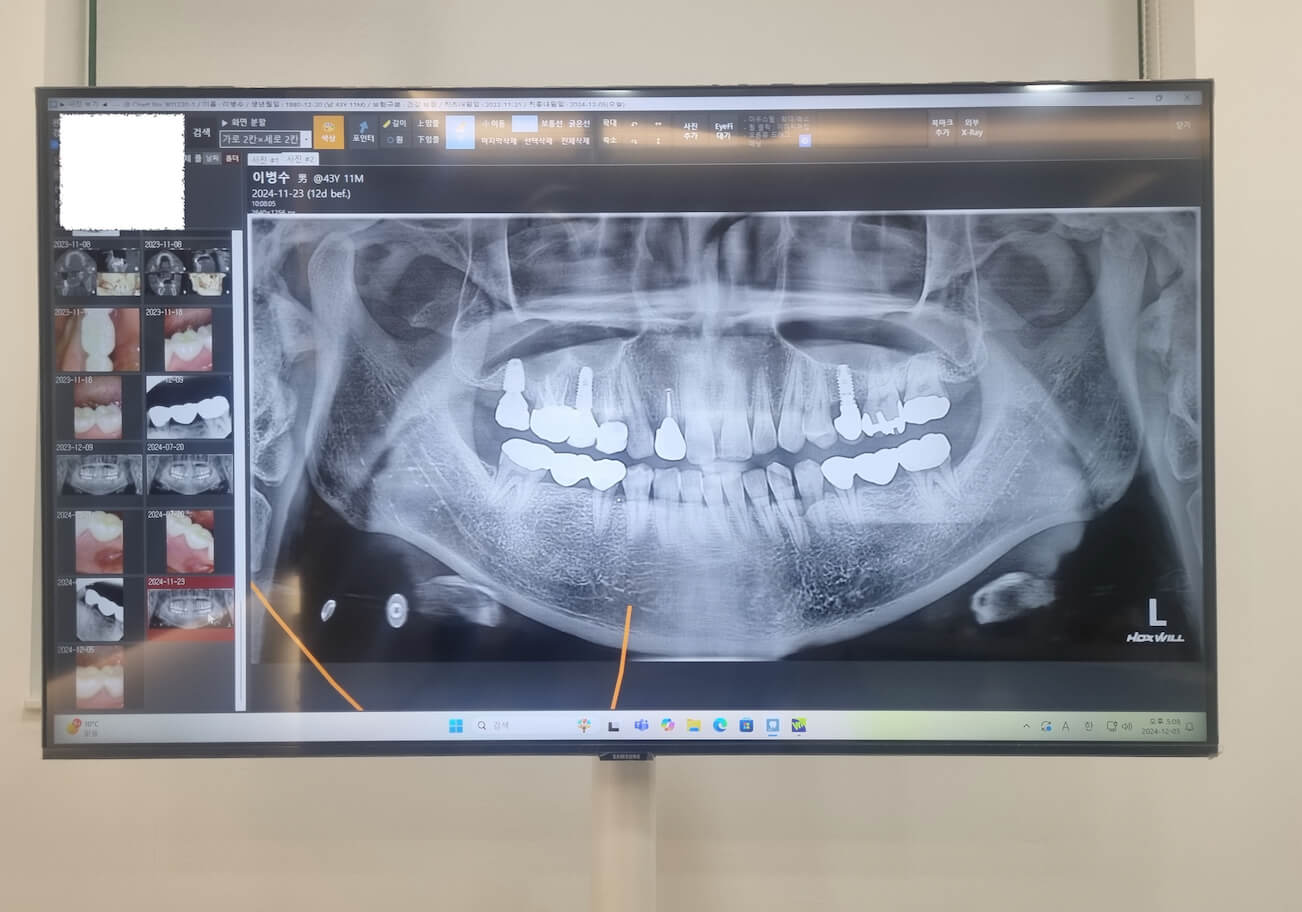

요즘에 치과에 가면 임플란트도 크라운을 지르코니아로 합니다. 브릿지도 왠만하면 강도와 심미성이 뛰어난 지르코니아 크라운으로 하는데 저는 임플란트 지르코니아가 깨어져서 입안에 상처가 났으며, 이번에 지르코니아 브릿지 3개짜리가 깨지고 또깨져 3번째 치아 브릿지를 하게 되었습니다.

임플란트 지르코니아는 1년 6개월만에 깨져서 치과에서 무료료 메탈로 다시 크라운을 제작해 주었으며, 얼마뒤 6개월전쯤 깨져서 다시 지르코니아 크라운으로 A/S받은 지르코니아 브릿지가 또 똑같은 부위가 깨져서 치과에 갔더니 강도가 쎈 메탈 브릿지로 다시 해준다고 합니다.

소비자로써 화가 나는건 임플란트를 해넣은 크라운도 지르코니아라서 깨져서 보다 저렴한 메탈제품으로 크라운을 만들게 되었고, 심미성이 뛰어나고 잇몸에 부작용이 없다고 골드 크라운대신 지르코니아 크라운으로 브릿지를 했는데 2년도 안되서 2번이나 깨졌습니다.

이전에 해넣은 골드 크라운 브릿지는 20년 넘어서 갈았고 옆에 3개짜리 골드 브릿지는 24년이 넘어가는데 아직도 사용하고 있는데 말입니다. 브릿지를 교체할때 제거하고 할때마다 마취를 해야하고 기존 브릿지를 제거하기 위해 갈아야 하는 이런시간이 거이 1시간정도 걸립니다.